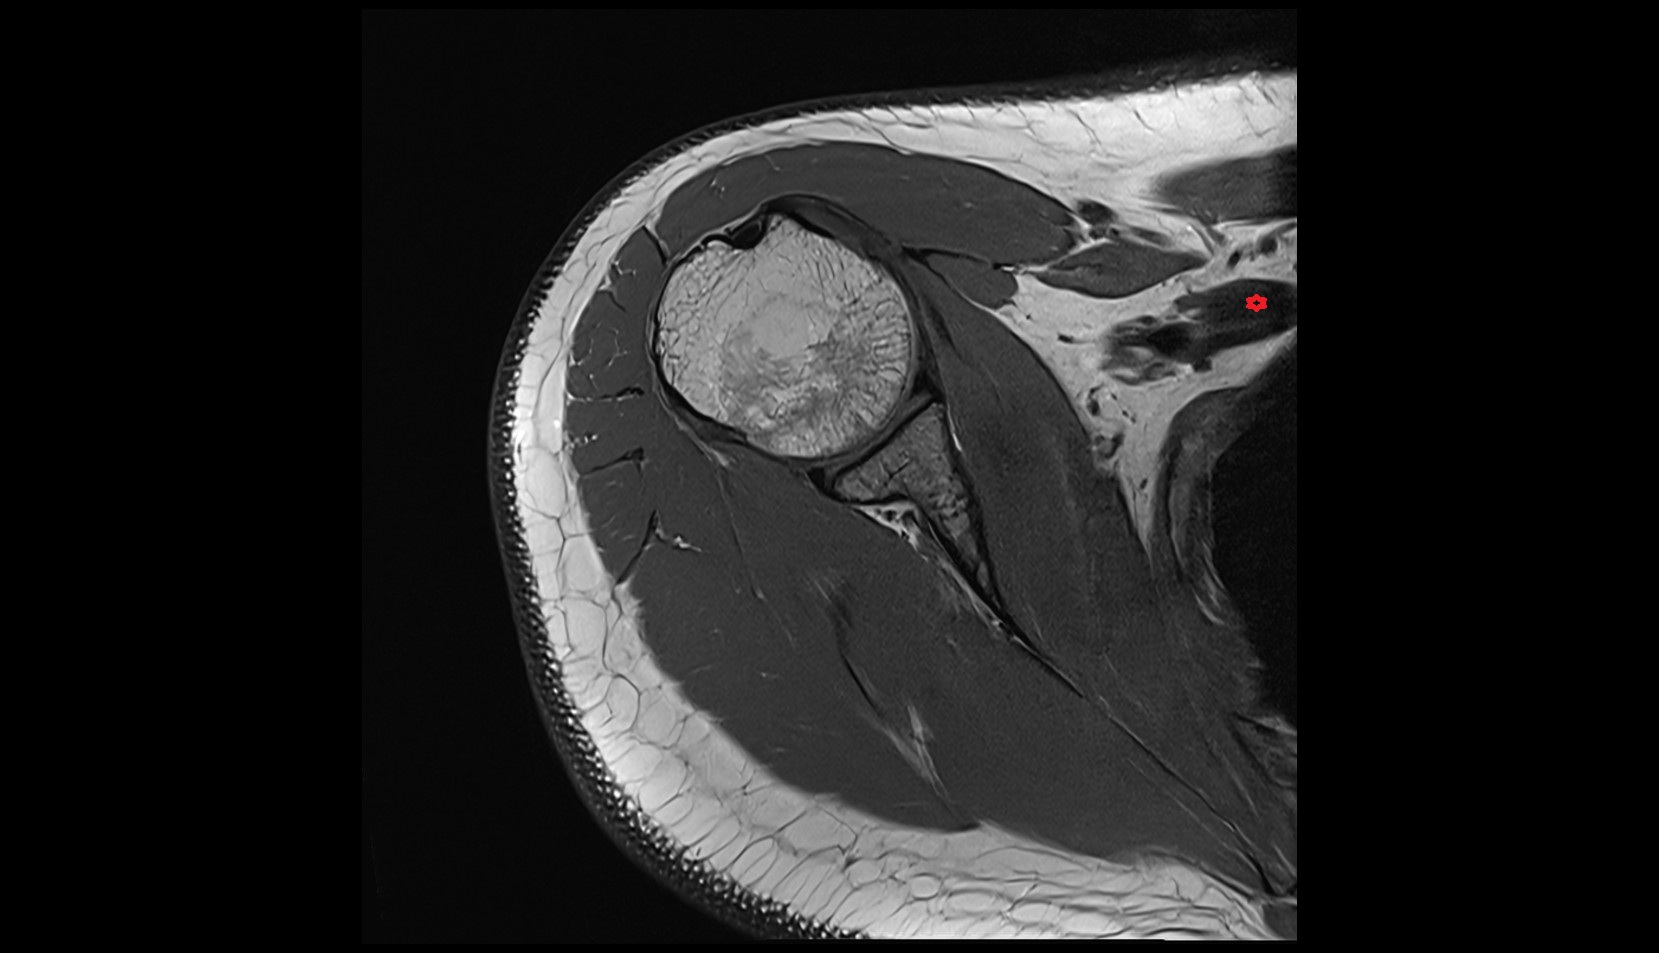

- Shoulder joint (glenohumeral joint)

- Glenoid fossa

- Head of humerus

- Supraspinatus tendon

- Infraspinatus tendon

- Subscapularis tendon